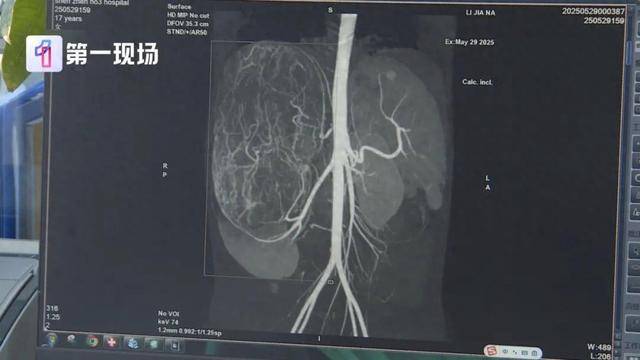

17岁女孩确诊癌症!买衣服时店员看出端倪……这个细节很重要!

广东17岁女孩婷婷(化名) 今年还在读高二 前段时间 妈妈带着她去逛街买衣服 试裤子的时候店员来帮忙 感觉孩子身形消瘦 但是肚子却有点大 于是建议妈妈带她去医院...